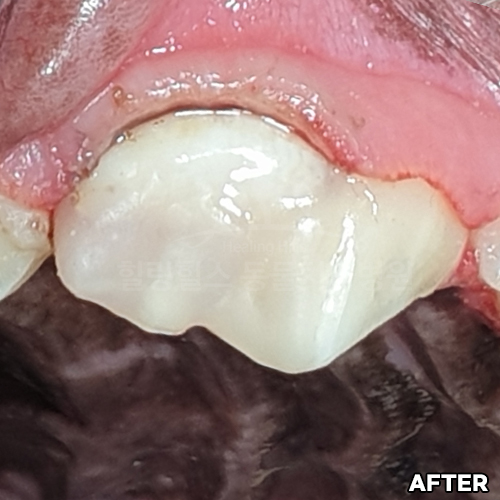

[신경치료 4개월 후 사라진 치근단농양!!]

샘플